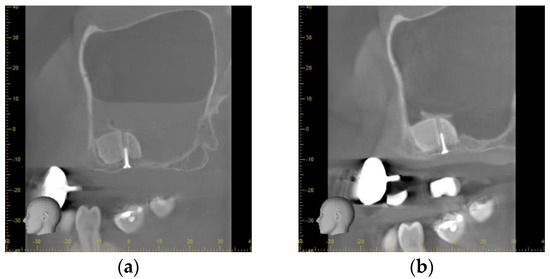

Directly after the insertion of the bone substitute, the cone beam computed tomography confirmed the correct position of the scaffolds according to the planned position. On the left side, a slight gap between the palatal bone wall and the scaffold was observed. The bone lids used to access the sinuses were located on the cranial site of the scaffolds. As a consequence of the small perforation of the Schneiderian membrane, a level of liquid was obvious in the left maxillary sinus whereas on the right side a slight swelling was observed (Figure 5a).

Figure 5.

Radiographical outcome (a) Sagittal plane of the left maxillary sinus directly after augmentation. An air-fluid-level of blood is visible after a small perforation of the Schneiderian membrane. The scaffold is tightly fixed to the host bone by the screw. (b) Sagittal plane of the left maxillary sinus prior to implant placement. The scaffold is showing sufficient osseointegration. The bone lid is visible cranial of the scaffold. No sign of inflammation or mucosal swelling is detectable in the sinus. (c) Panoramic radiograph after implant uncovering. A sufficient osseointegration of the scaffolds and the dental implants without any signs of peri-implant osteolysis is obvious. No sign of inflammation of the maxillary sinuses is detectable.